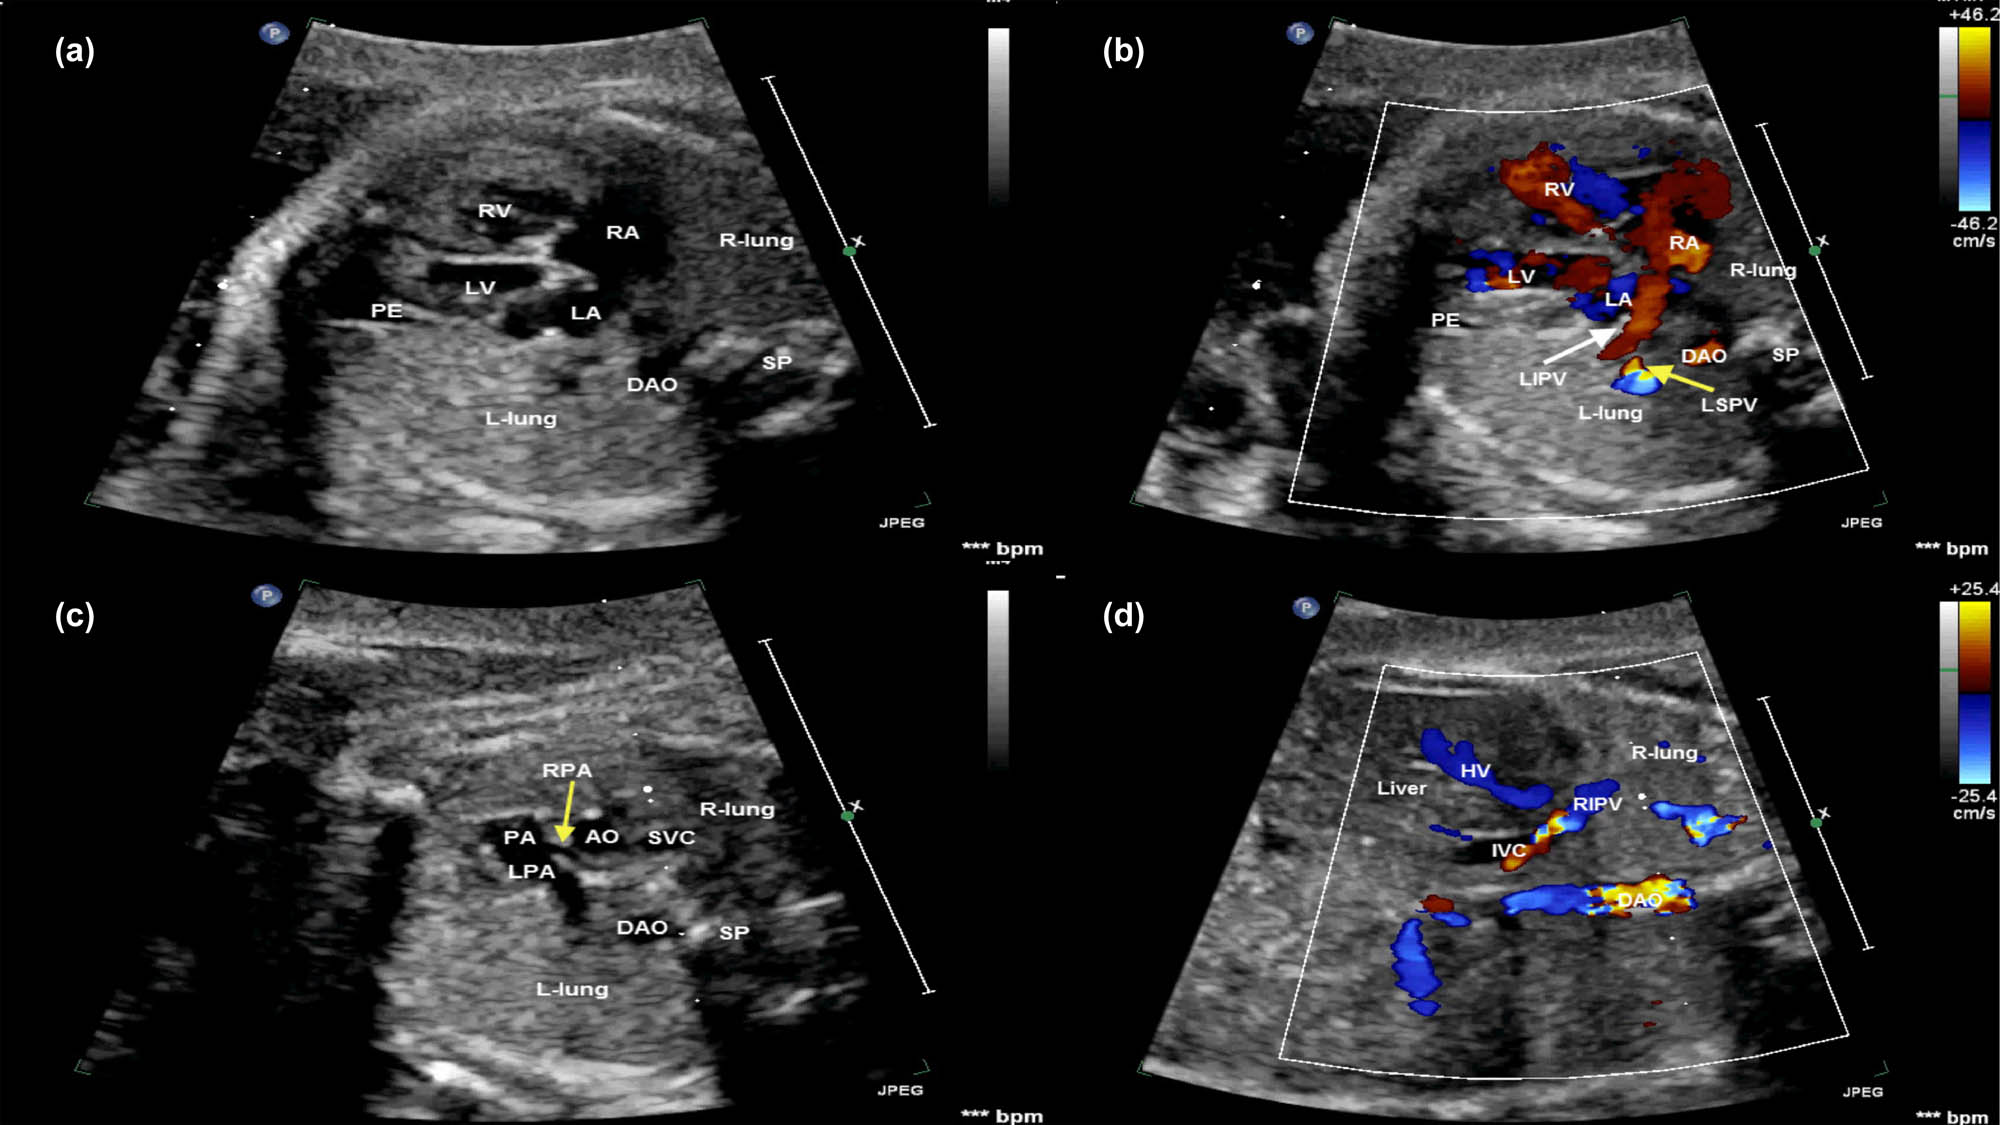

All sonographic findings are characterized by color and power Doppler imaging, demonstrating the affected right pulmonary vein draining into the IVC below the diaphragm or the junction of the IVC and the RA on the coronal and sagittal views of the thorax in all fetuses (Figures 1 and 2). A solitary small abdominal aortopulmonary collateral was found by the prenatal echocardiography only in case 6.

Fetal echocardiogram of case 6 at the time of diagnosis. (a) The four-chamber view demonstrated the heart shifted to the right, the echo of bilateral lung tissue was consistent and normal, and the right lung was dysplastic. A small PE was seen at the apex of the LV. (b) Color Doppler showing the LPV (white and yellow arrows) flowed back into the LA and no normal right pulmonary vein flowed back into the LA. (c) The bifurcation of the PA view demonstrating that the origin of the pulmonary branch was normal and the inner diameter of the RPA (yellow arrow) was narrow than the left PA. (d) Color Doppler showing the RIPV passed through the diaphragm and drained into the IVC on a coronal view. AO, aorta; DAO, descending aorta; HV, hepatic vein; IVC, inferior vena cava; LA, left atrium; LIPV, left inferior pulmonary vein; L-lung, left-lung; LPA, left pulmonary artery; LV, left ventricle; PA, pulmonary artery; RA, right atrium; RIPV, right inferior pulmonary vein; R-lung, right-lung; RPA, right pulmonary artery; RSPV, right superior pulmonary vein; RV, right ventricle; SP, spine.